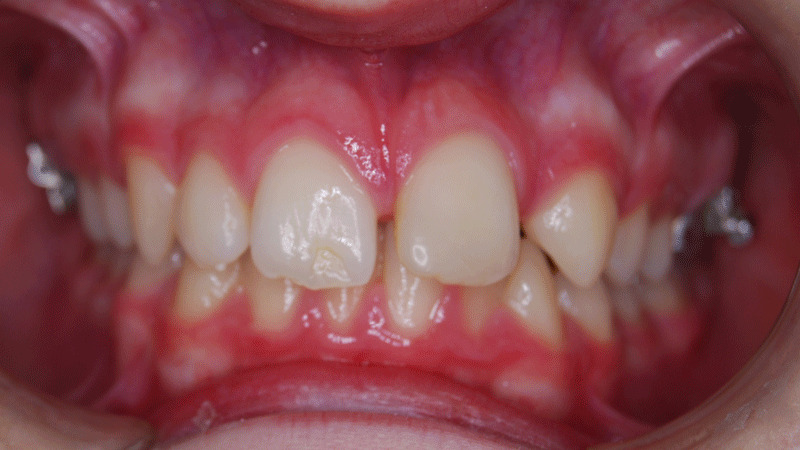

The deep bite, also known as overbite, is a problem of malocclusion in which top teeth excessively overlap the lower ones.

Obviously, the overbite is the distance between the edge of the upper and lower central incisors vertically. Clearly, the deep bite considered normal has the upper front teeth exceeding approximately 1/3 of the lower ones.

Specifically, we speak of a severe overbite, when it reaches a maximum degree. That is to say, when the upper middle front teeth completely cover the lower ones. Sometimes, it is also known as a complete overbite.